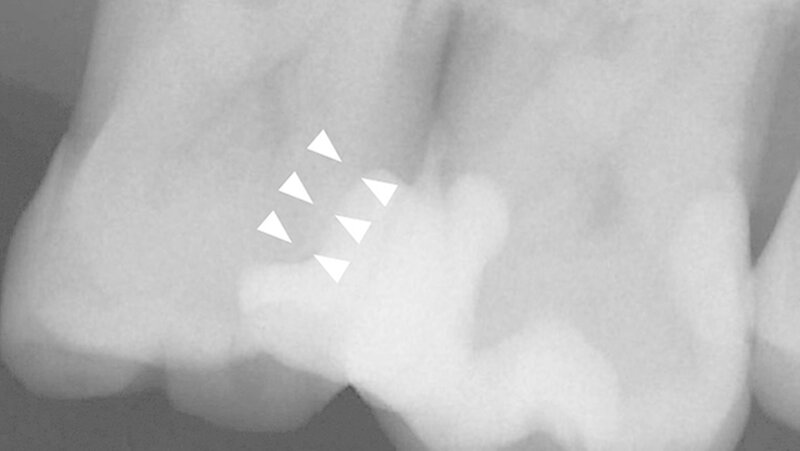

Anschließend erfolgte die Kariesexkavation mit Rosenbohrern unter optischer Kontrolle mit einem OP-Mikroskop. Die Kavität wurde im Verlauf der Exkavation mehrmals mittels FACE (fluoreszenzgestützter Kariesexkavation, SIROinspect, Sirona) auf Residualkaries überprüft [Buchalla W et al., 2013].

Bei der vollständigen Kariesentfernung kam es nicht zu einer Freilegung der Pulpa (Abbildung 3). Anschließend wurde eine Metallmatrize (HaweTofflemire Matrize, Kerr Dental) angelegt und verkeilt. Die Kavität wurde gereinigt und getrocknet.